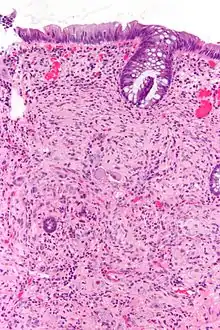

Pathologie

Pathologiquement, les ganglioneuromes sont composés de cellules ganglionnaires, de cellules de Schwann et de tissu fibreux[4]. Les ganglioneuromes sont des tumeurs solides et fermes, généralement de couleur blanche à l'œil nu.